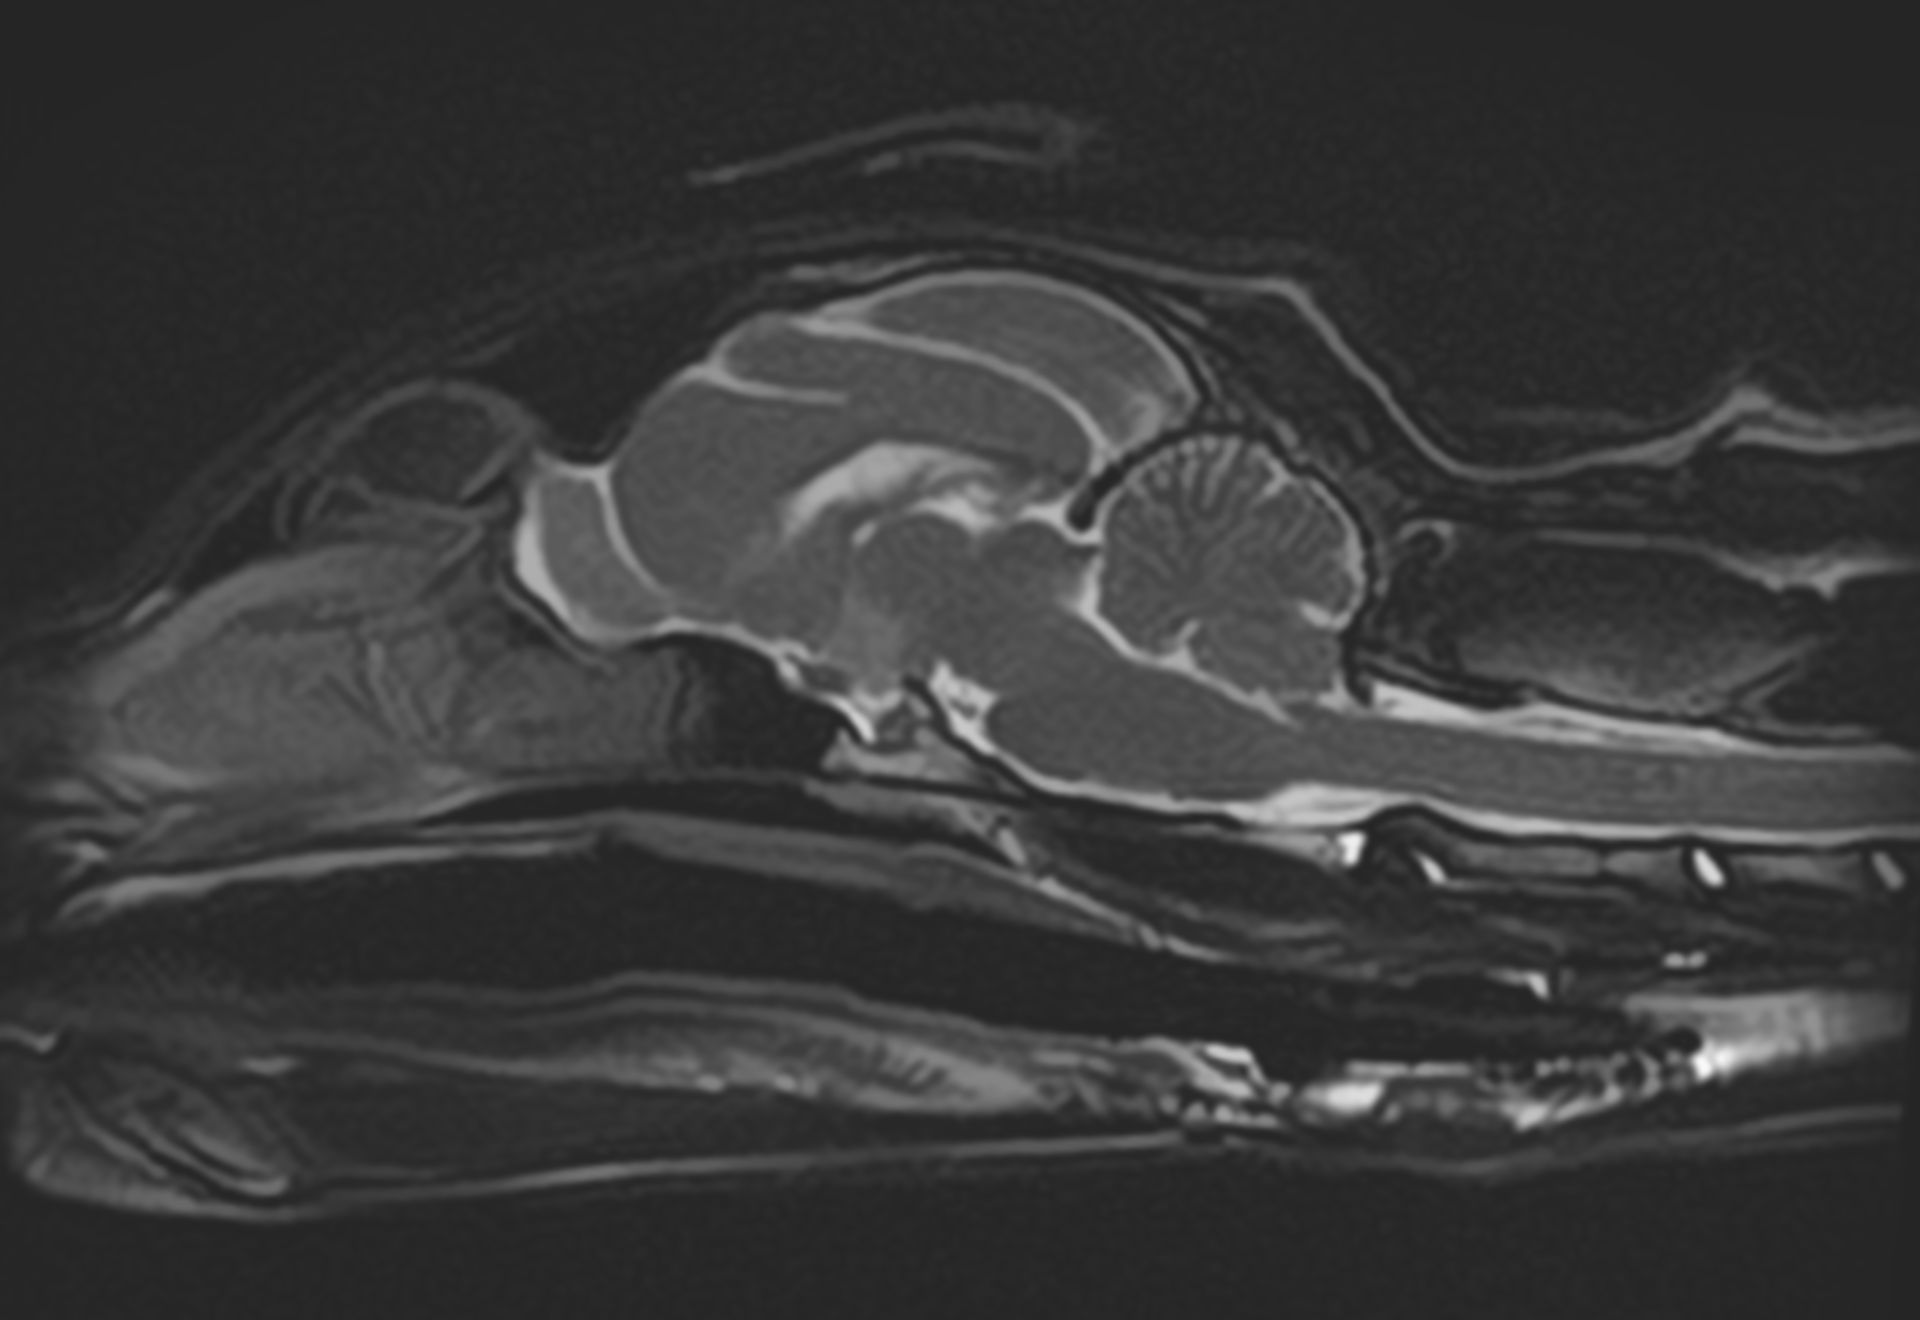

Pour compléter le scanner, le CHV dispose d’une IRM haut champ (1,5T) ORIAN, particulièrement performante pour :

- Articulations et tissus mous (ménisques, cartilages, ligaments), quand une analyse fine des tissus est nécessaire.

Notre IRM présente des gradients élevés ainsi qu'une grande ouverture de tunnel permettant de réduire les temps d'acquisition et d'augmenter la résolution spatiale de nos images.